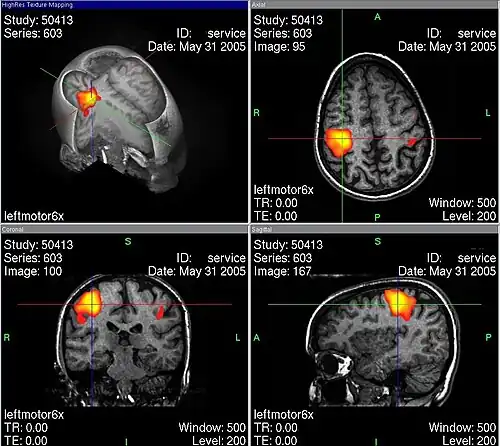

Durch fMRT-Aufnahmen ist es möglich, Durchblutungsänderungen von Hirnarealen sichtbar zu machen, die auf Stoffwechselvorgänge zurückgeführt werden, welche wiederum mit neuronaler Aktivität in Zusammenhang stehen. Hierbei macht man sich die unterschiedlichen magnetischen Eigenschaften von oxygeniertem und desoxygeniertem Blut zunutze (BOLD-Kontrast). Bei der Aktivierung von Kortexarealen kommt es zu einer Steigerung des Stoffwechsels, wodurch das aktivierte Areal mit einer überproportionalen Erhöhung des Blutflusses reagiert (sog. neurovaskuläre Kopplung). Dadurch erhöht sich die Konzentration von oxygeniertem (diamagnetischem) relativ zu desoxygeniertem (paramagnetischem) Hämoglobin. Über den intermolekularen Elektronendipol-Kerndipol-Relaxationsmechanismus bewirkt diese Konzentrationsänderung eine Veränderung der effektiven transversalen Relaxationszeit der beobachteten Wasserstoff-Kernspins und führt damit zu einer Signaländerung in der MRT. Um so Rückschlüsse auf den Ort einer neuronalen Aktivität zu ziehen, wird das Magnetresonanz-Signal des Gewebes zu zwei Zeitpunkten verglichen – z. B. im stimulierten oder Experimentalzustand einerseits sowie im Ruhe- oder Kontrollzustand andererseits. Die Aufnahmen können durch statistische Testverfahren miteinander verglichen und die statistisch signifikanten Unterschiede (die den stimulierten Arealen entsprechen) räumlich zugeordnet und dargestellt werden.

Bei einer Untersuchung des Gehirns zu Versuchszwecken kann dem Probanden im dritten Teilscan zum Beispiel ein wiederholter Reiz präsentiert werden. Häufig wird der Reiz mit einer Aufgabe für den Probanden verknüpft, etwa der Aufforderung, bei jedem gezeigten Objekt X eine Taste zu drücken. Den meisten Versuchen gemein ist die häufige Wiederholung der Aufgabe. So kann dann durch statistische Verfahren ein Vergleich aufgezeichneter Daten aus der Reizphase mit denen aus der Ruhephase stattfinden. Der hieraus berechnete Unterschied wird dann in Falschfarben auf den zuvor durchgeführten anatomischen MR-Scan projiziert.